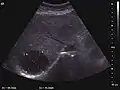

Liver abscess (2D and CEUS). 2D Examination reveals the fluid nature of the mass and imprecise delineation. CEUS examination shows congestion in the surrounding liver parenchyma and excludes a vascular tumor.

Liver abscess have heteromorphic ultrasound appearance, the most typical being that of a mass with irregular shapes, fringed, with fluid or semifluid content, with or without air inside. Doppler examination shows the lack of vessels within the lesion. CEUS exploration shows hyperenhancement during arterial phase close to the lesion, this being suggestive of a liver parenchymal hyperemia. During venous and sinusoidal phase the pattern is hypoechoic, and the central fluid is contrast enhanced. CEUS examination is useful because it confirms the clinical suspicion of abscess. In addition, it allows for an accurate measurement of the collection size and an indication regarding its topography inside the liver (lobe, segment).